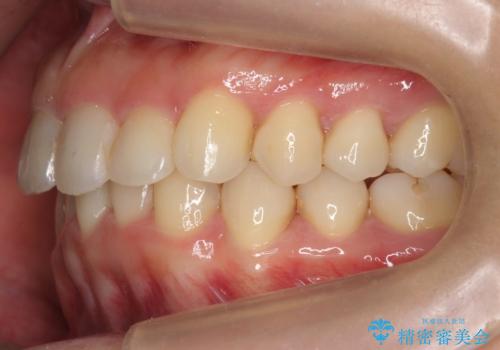

出っ歯 下の歯のガタガタ 下の前歯のみ1本抜歯 マウスピースで1年

下の前歯のがたつきがひどく、非抜歯では難しい状態でした。

古典的な方法では4本抜歯した後、ワイヤー矯正という方法も選択肢には上がりましたが、下の前歯を1本だけ抜くことにし、マウスピースで短期間で治療を終わらせるようにしました。

治療も比較的短期間で終わり、大変喜んでいただきました。

下の前歯を1本抜くと上下の正中はあいませんが、ほとんど目立ちません。